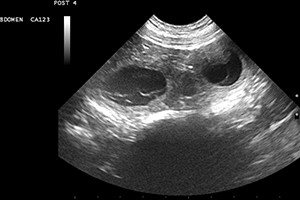

Eine turbulente Woche voller Sorgen liegt hinter uns: Annie hat leider eine Pyometra (Gebärmutterentzündung) entwickelt und musste am Dienstag Notkastriert